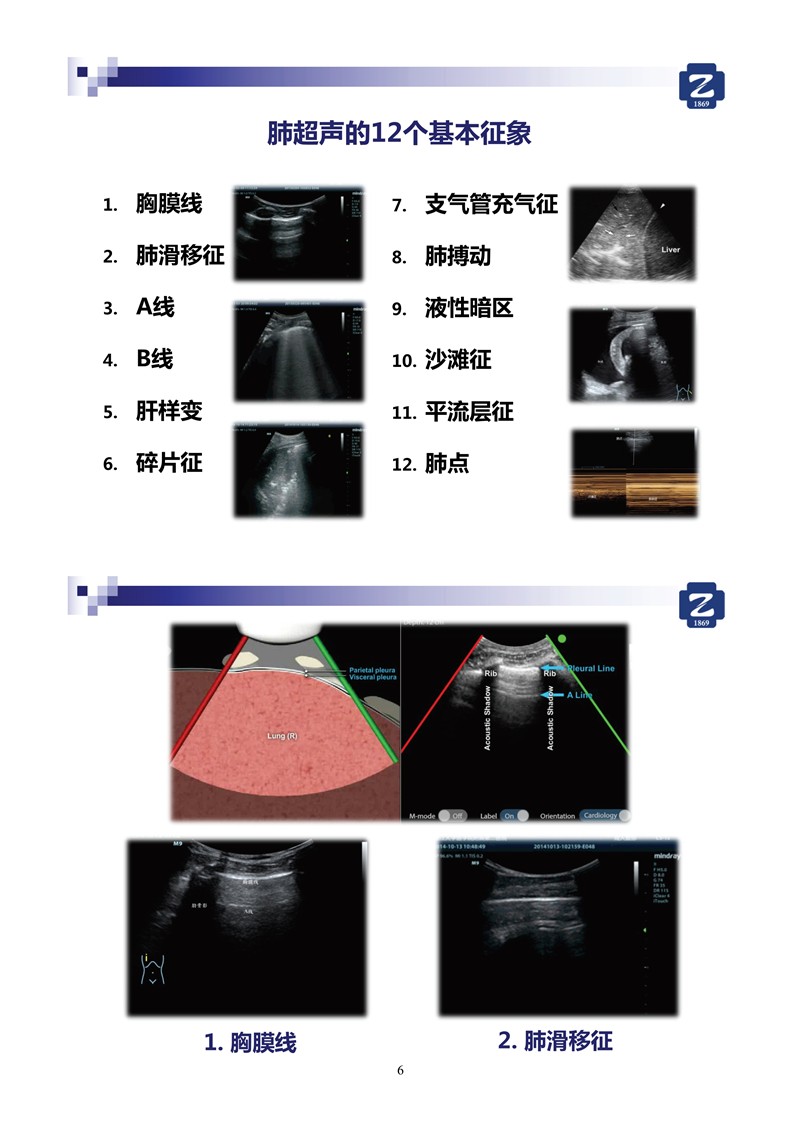

第一版新型冠狀病毒肺炎超聲診斷實(shí)用手冊(cè)(全文)

新冠肺超聲實(shí)用手冊(cè)(2)_35.jpg